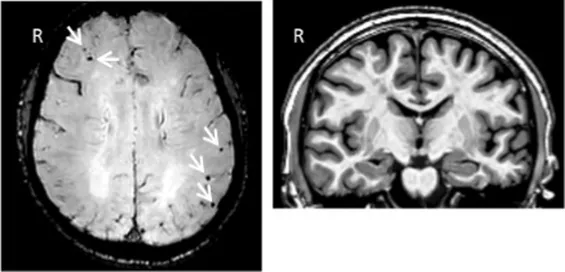

| Clinical findings | CSF and APOE | SWI and T1-weighted MRI scans | Proposition of ongoing neuroinflammatory processes |

| Case 5: a 64 y.o. man who was referred for a memory complaint. At screening, he had 24/30 MMSE and impairment on episodic memory, denomination and categorical verbal fluency tests. On MRI, multiple lobar microbleeds without hemisiderosis were observed as well as WMH (Fazekas’s score of 8/9) and moderate cortical atrophy. | Aβ42: 208 P-tau: 184 T-tau: 1449 APOE E3/E3 TSPO MAB | ![]() | ![]() Toxic neuroinflammation associated with mixed angiopathy and AD pathological progression. |

All fourth patients are right-handed. TSPO PET imaging showed SUVR relative to the cerebellar cortex and is represented in standard space in the same slice and intensity scale, whereas MRI scans are shown in native space. Cerebrospinal fluid AD biomarker values were abnormal for the four patients (see the method section for details).

Aβ42, amyloid-β 42; AD, Alzheimer’s disease; APOE, apolipoprotein E; CAA, cerebral amyloid angiopathy; CSF, cerebrospinal fluid; MMS, mini-mental state examination; MRI, magnetic resonance imaging, P-tau, phosphorylated tau; SWI, susceptibility-weighted imaging; T-tau, total-tau; TSPO, translocator protein; WB, whole brain; WMH, white matter hyperintensities.